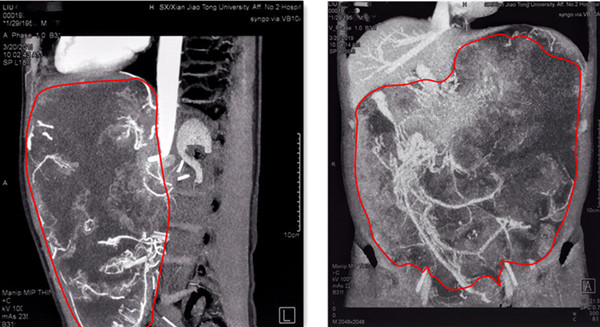

在完善术前检查过程中,发现该患者双肺多发肺大泡,经呼吸及危重症医学科会诊认为肺功能未提示全麻绝对禁忌,肺大泡存在术中破裂风险;下腹部CT平扫及增强扫描发现盆腹腔内巨大不规则囊实性肿块,部分边界欠清、临近腹腔结构受压移位、增强后病变呈明显不均匀强化,其内可见多发迂曲血管影;进一步CTA、CTV提示:主要由腹腔干、胃十二指肠动脉分支供血,经粗大引流静脉汇入脾静脉。为制定安全有效的手术方案,普外科专家组进行多次术前评估,并组织多学科MDT讨论,同时向医务部报备重大手术计划。